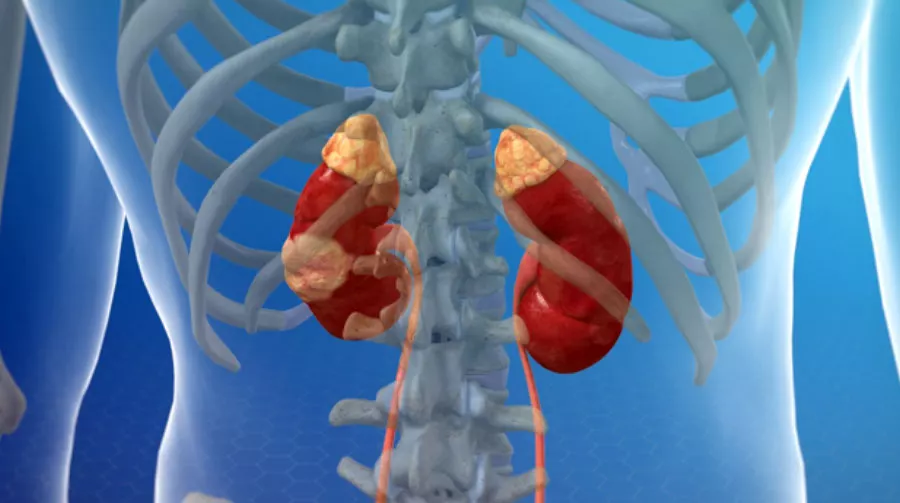

Медицинские изображения и объяснения агенезии почки